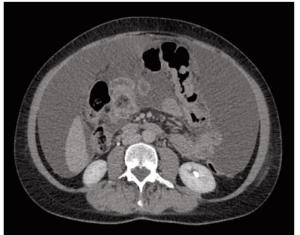

An otherwise healthy 58-year-old woman with a history of breast cancer presents to the clinic with newly diagnosed metastatic disease; eventual abdominal CT showed a mass in the transverse colon with ascites and peritoneal nodularity. What is the best initial systemic treatment for her?